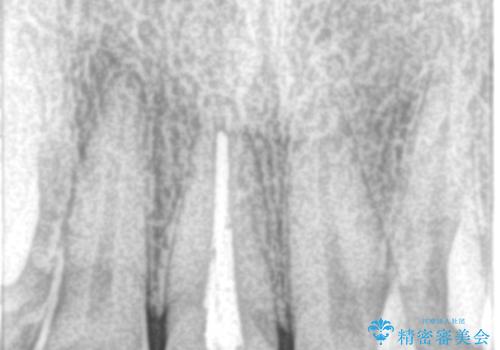

- 前歯の色が変色してきて、気になるとのことで来院されました。

オールセラミックを装着することで改善することとしました。